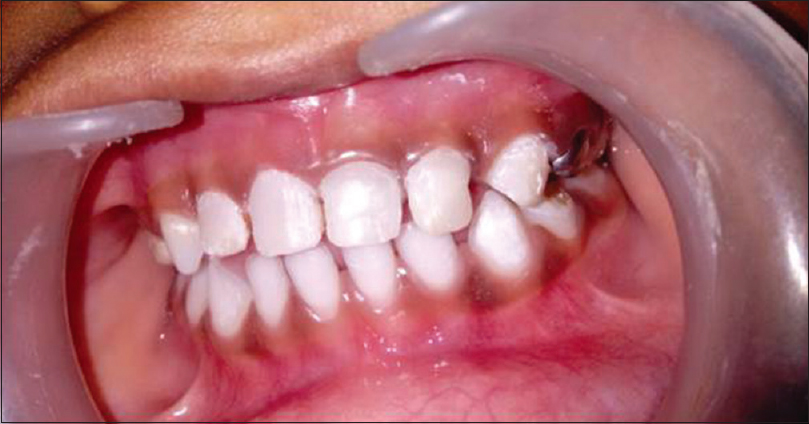

A single-visit pulpectomy (root canal treatment) of the upper left middle and lateral incisors was performed under local anesthesia [Figure 2]. Antibiotics and analgesics were prescribed, and the patient was recalled 3 days later for surgery. The patient’s parents insisted on tooth rehabilitation for esthetic reasons and because the eruption of permanent teeth takes a long time. The biological crown was created keeping the patient’s dental health in mind, as well as the parents’ wishes.

thumb

Figure 2: Postobturation radiograph